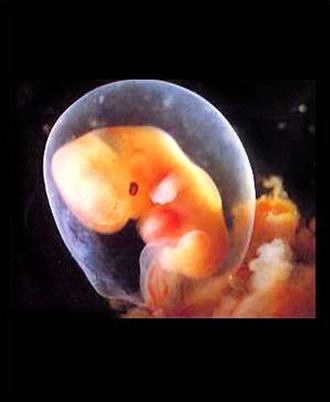

- 10주 이전

- 질 초음파 (1회/2주)

- 산모종합검사 (풍진, 간염, 매독, 에이즈, 빈혈, 혈액형, 갑상선, 소변검사)